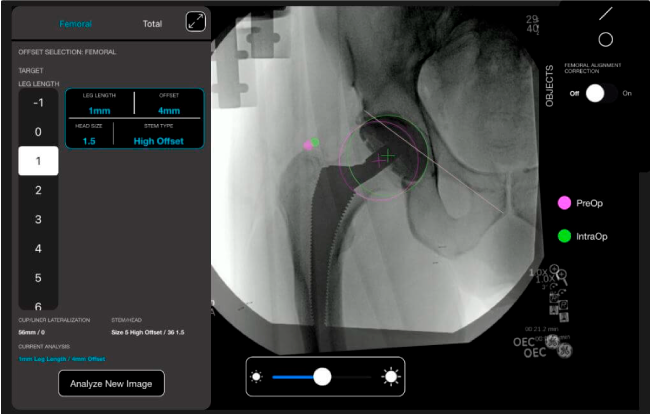

Nuestro sistema de navegación digital VELYS HIP NAVIGATION ™ para cirugía de cadera, es una tecnología innovadora y no invasiva diseñada para apoyar la toma de decisiones de los médicos en tiempo real y basada en datos; aumentando la precisión y dando mejores resultados.

El sistema de navegación digital VELYS HIP NAVIGATION ™ para cirugía de cadera, es una tecnología innovadora y no invasiva diseñada para potencializar la toma de decisiones en tiempo real y basada en datos; aumentando la precisión y mejorando los resultados a corto, mediano y largo plazo para los pacientes.

Planeación preoperatoria mediante la creación de plantillas digitales para reemplazo de cadera y análisis intraoperatorio

Datos procesables en tiempo real para la toma de decisiones.

Favorece la restauración biomecánica del offset femoral.

Desplazamiento y offset para posicionamiento óptimo del componente (vástago) femoral.

Anotaciones digitales y herramientas de análisis de longitud de pierna.

Con tecnología ONETRIAL® que calcula automáticamente el cambio en la longitud de la pierna y el desplazamiento para todas las combinaciones de implantes en una tabla fácil de leer.